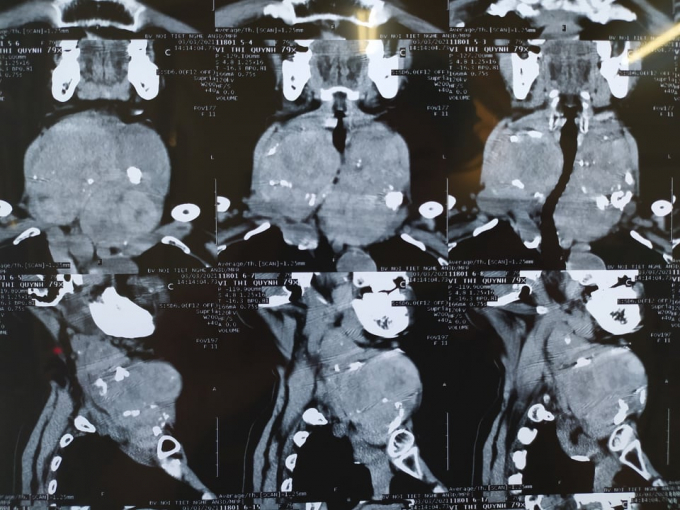

Tại đây, qua thăm khám bác sĩ xác định hai thùy kích thước rất lớn, có nhiều khối tỷ trọng hỗn hợp, một vài khối trong có vôi hóa, các khối phát triển lan rộng ra xung quanh gây đè dây thanh và các cấu trúc lân cận, phát triển sâu xuống trung thất, vượt qua đường nối giữa hai khớp ức đòn. Cụ thể thùy phải có khối hỗn hợp âm, khối lớn kích thước 7,2 x 4,7 cm, thùy trái của bệnh nhân có nhiều khối hỗn hợp bờ đều, khối lớn kích thước 5,8 x 3,7cm. Bệnh nhâ được chỉ định mổ cắt khối u tuyến giáp.

Xác định đây là một ca phẫu thuật khó, vì bệnh nhân đã lớn tuổi, cộng với khối u có kích thước lớn chèn ép gây nhuyễn khí quản và đè đẩy khí quản dẫn đến khó khăn trong gây mê và quá trình hậu phẫu. Bên cạnh đó trong khối u “khổng lồ” có rất nhiều mạch máu tăng sinh lớn gấp 4 - 5 lần so với mạch máu của khối u bình thường nên trong quá trình phẫu thuật dễ làm tổn thương mạch máu lớn xẩy ra mất máu rách thực quản. Khối u “khổng lồ” chèn ép gây biến dạng cấu trúc giải phẫu nên sẽ gây khó khăn trong quá trình phẫu thuật.